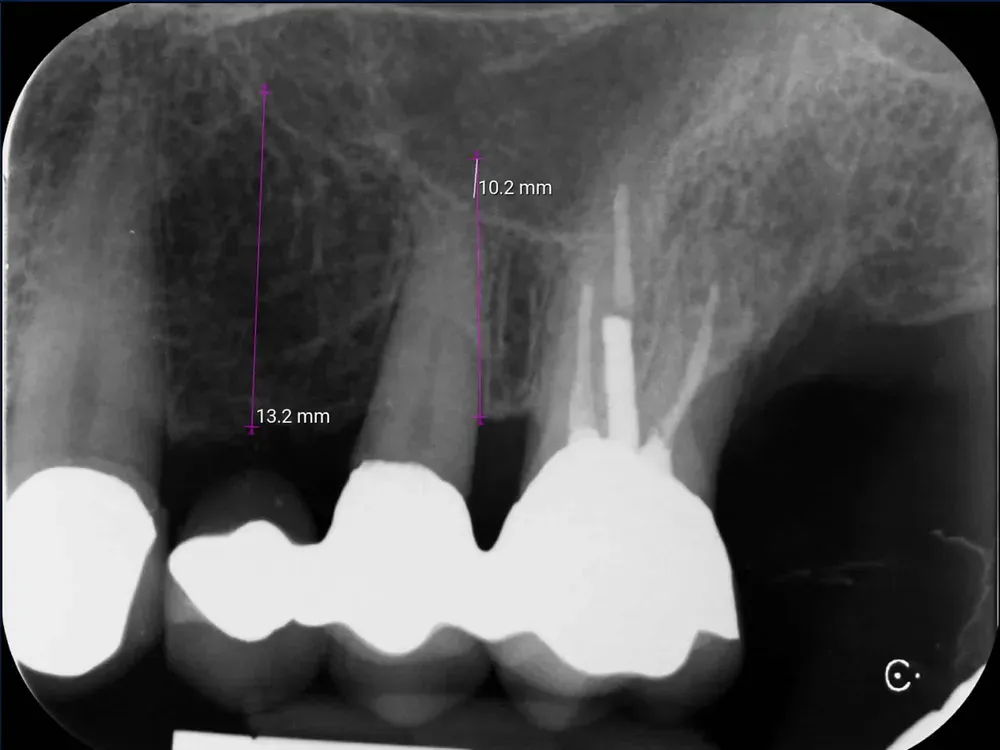

Si presenta con una dolenzia nel secondo quadrante. All’esame clinico e radiografico, riscontro una carie radicolare e una tasca parodontale con ascesso acuto dell’elemento di ponte 2.5. In base alla conformazione del difetto e soprattutto per la profondità della carie, lo classifico come “non trattabile” e procedo alla pianificazione di un trattamento con inserimento di impianti in zona 2.4 e 2.5, previo taglio del ponte tra 2.5 e 2.6 per conservare l’elemento 2.6 come corona singola.

Radiografia dentale periapicale preoperatoria di un elemento di ponte con carie profonda tasca parodontale e ascesso acuto non trattabile.

Radiografia periapicale preoperatoria con l’elemento di ponte 2.5 affetto da carie profonda e tasca parodontale con ascesso acuto non trattabile.

La CBCT dimostra l’anatomia atrofica della zona, con la vicinanza del pavimento del seno mascellare e la significativa perdita di sostanza palatale dovuta all’infezione parodontale.

CBCT di elemento dentario 2.5 affetto da carie e tasca parodontale acuta

CBCT dell’elemento 2.5 con evidenza della vicinanza del seno mascellare e della distruzione del parodonto, soprattutto sul versante palatino.